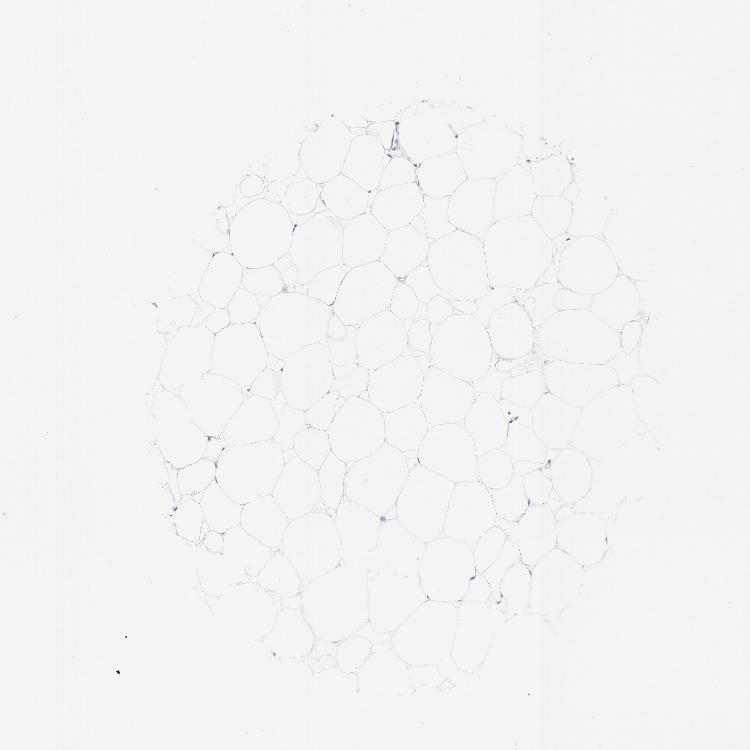

ADIPOSE TISSUE - Antibody stainingi

Antibody staining in the annotated cell types in the current human tissue is reported as not detected, low, medium, or high, based on conventional immunohistochemistry profiling in selected tissues. This score is based on the combination of the staining intensity and fraction of stained cells.

Each image is clickable and will lead to virtual microscopy that enables deeper exploration of all samples and also displays staining intensity scores, fraction scores and subcellular localization as well as patient and tissue information for each sample.

Antibody HPA002465Antibody CAB000031

Adipocytes Not detectedNot detected